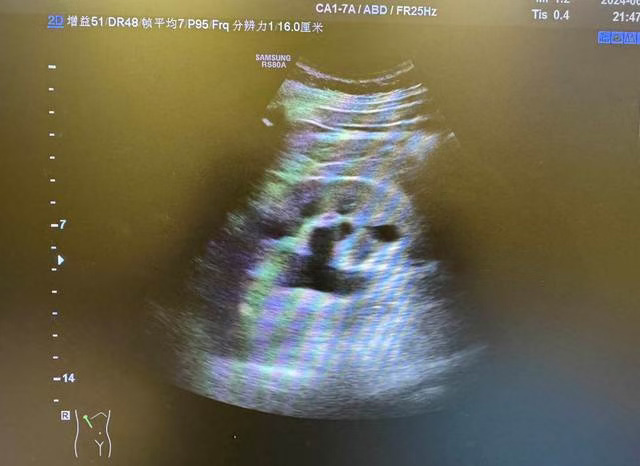

超聲檢查是其診斷的首選方法,因?yàn)槌暰哂兄庇^、簡易、省時、無痛苦、無放射線等優(yōu)點(diǎn),臨床上應(yīng)用廣泛。超聲能迅速判斷腎臟位置、外形、大小,在腎臟疾病的診斷、療效觀察和預(yù)后判斷方面有著十分重要的意義,現(xiàn)在已經(jīng)成為腎病患者的常規(guī)檢查。并且腎結(jié)石的體積都很小,有的呈泥沙狀,超聲在這方面分辨率非常高,在彩超下會顯示出非常明亮的強(qiáng)回聲團(tuán),并且在強(qiáng)回聲團(tuán)后方會有明顯的聲影。很小的腎結(jié)石在超聲下也可以檢查出,因此,腎結(jié)石在彩超下具有非常高的診斷率。但由于腸道內(nèi)容物對超聲具有干擾作用,超聲檢查輸尿管中下段結(jié)石的敏感性較低,可結(jié)合其他影像學(xué)檢查如CT檢查補(bǔ)充診斷。